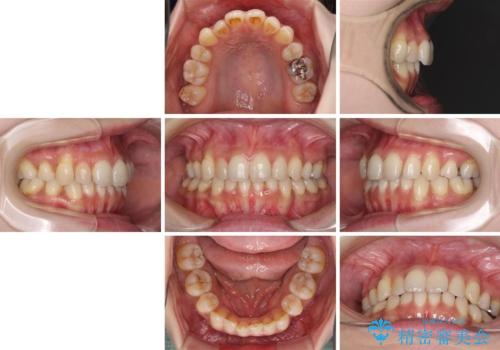

- 上下前歯の叢生を気にして来院された患者様です。

費用を抑え、期間もあまりかけずに治療をしたいとのことで、インビザライン・ライトを用いて矯正治療を行うこととしました。

インビザライン・ライトは、製作できるアライナーの枚数に制限があるため、移動可能な量に限りがあります。

一方で、半年程度で治療を終えることができるため、軽度の歯列不正の患者様には大変お勧めです。